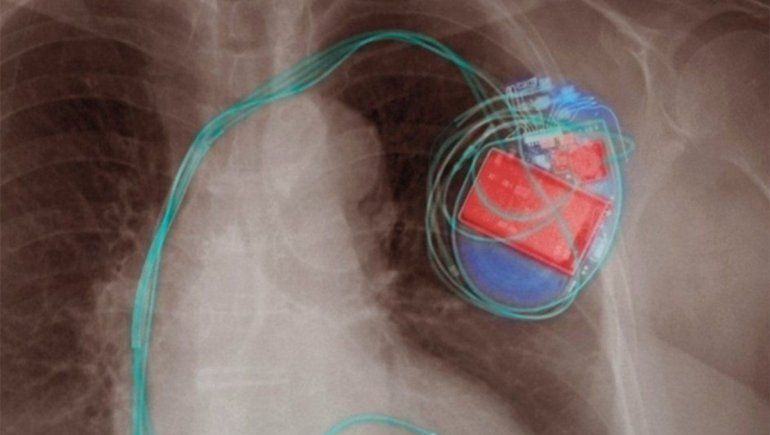

Los desfibriladores implantados envían impulsos eléctricos para regular los ritmos cardíacos anormales.

Por ejemplo, señaló, "los marcapasos y desfibriladores implantados pueden contener sensores que responden a imanes y radios cuando están en contacto cercano".